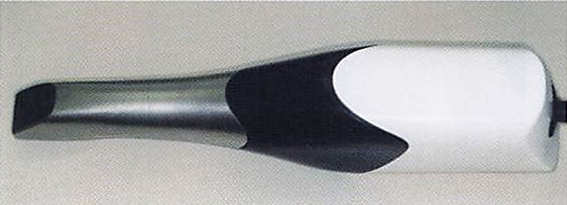

午前-46

適合試験材を用いた部分床義歯内面の状態の写真を別に示す。義歯調整を行うことになった。

使用する器材はどれか。2つ選べ。

a.ロビンソンブラシ

b.シリコーンポイント

c.カーボランダムポイント

d.タングステンカーバイトバー

解答を見る

b.c